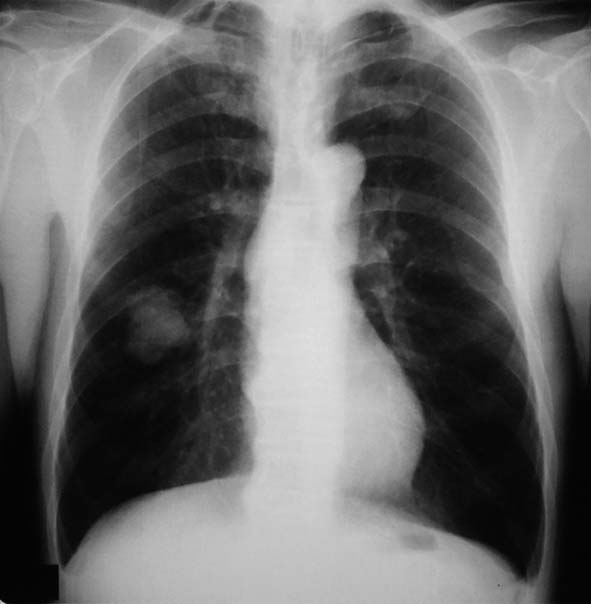

健診で2年ほど肺異常陰影を指摘されていたが自覚症状なく放置. 陰影が次第に増大, 精査のため受診する.

右肺下葉, S6bを主体に一部S9に広がる4.2x3.7x2.5cmの腫瘤. 辺縁凹凸不整, 胸膜に接し内部には不整形の小石灰化がある.肺癌疑い.気管支鏡TBBでは組織片が採取できなかった.

PETで原発巣にSUV max2.2の淡い集積. リンパ節には集積なし. 遠隔転移なし. 肺癌としてはPET集積が淡いが, cT2/1N0M0の肺癌であればstage1B~2Aとなり根治切除可能のためCTガイド下生検が施行された.